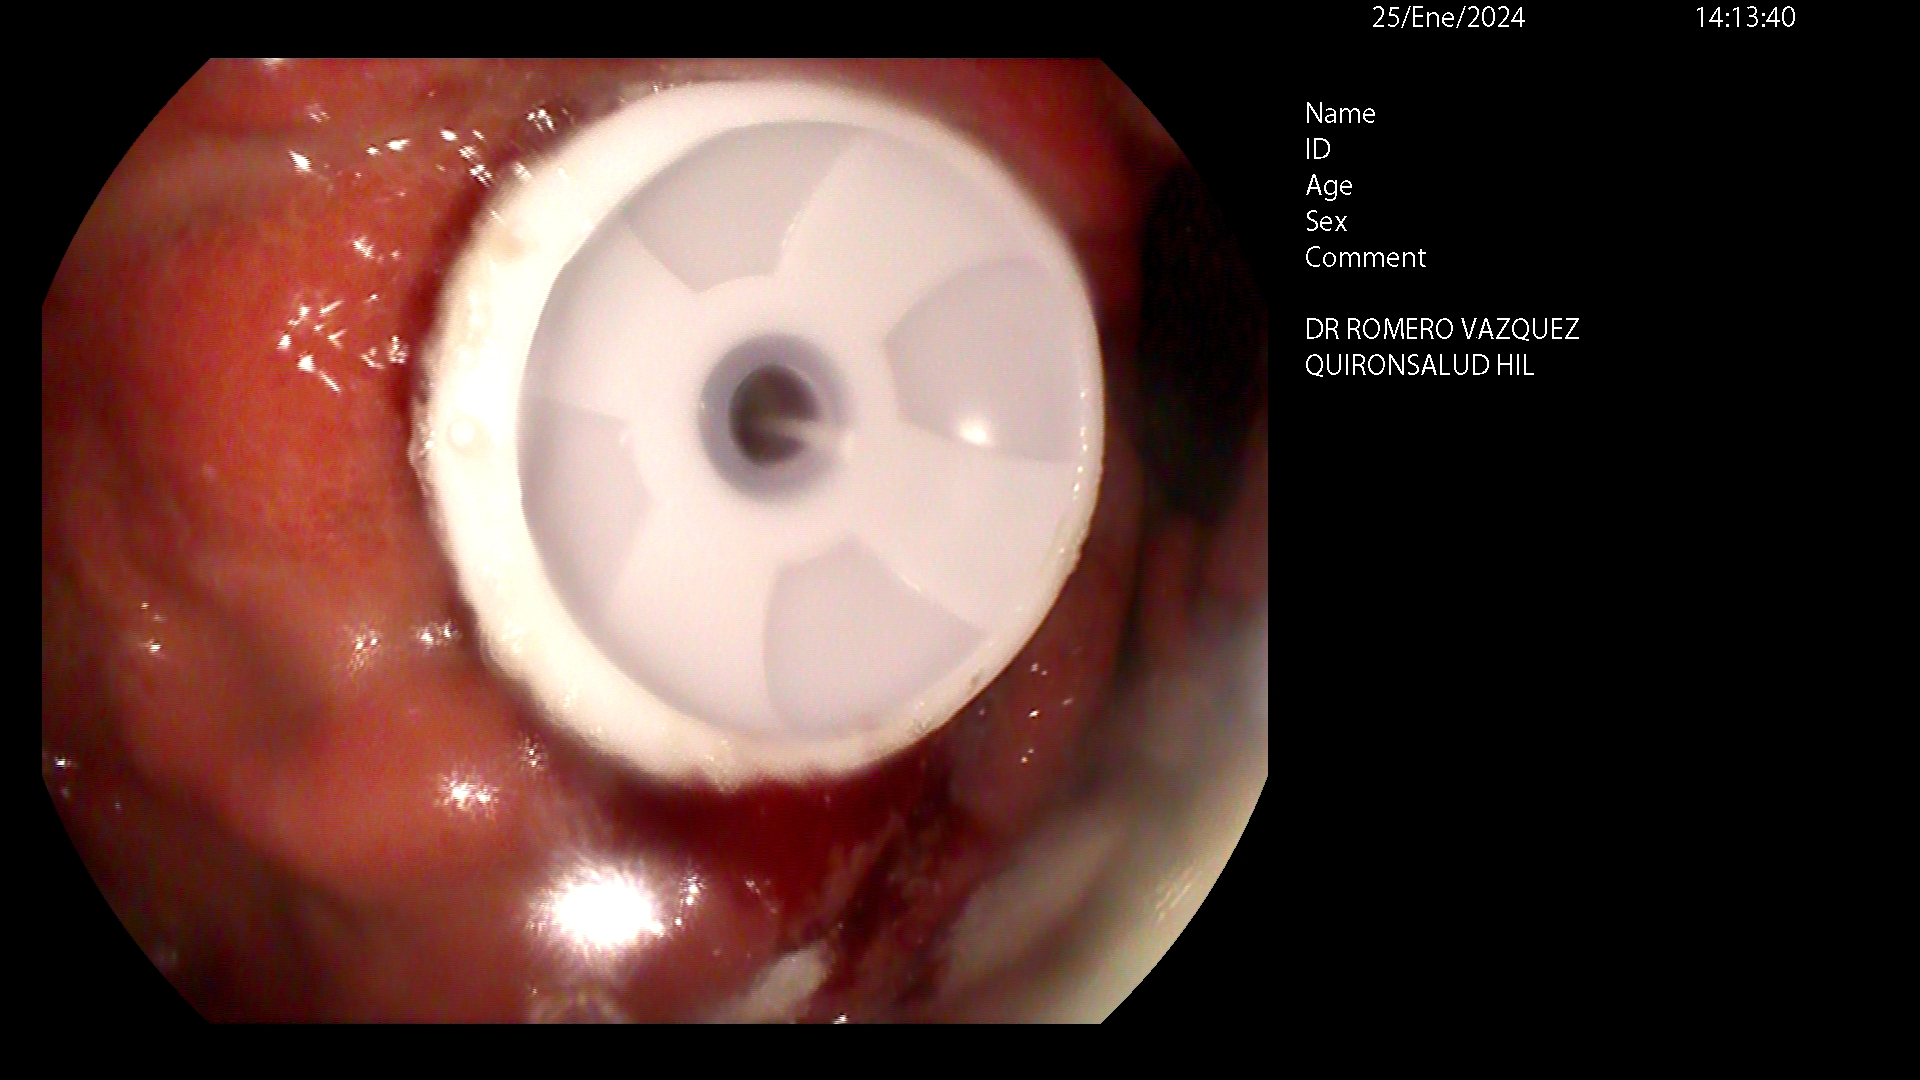

En esto casos, cuando hay que nutrir al paciente de forma crónica, es preferible un tipo de sonda conocida como gastrostomía endoscópica percutánea (GEP o PEG de las iniciales en inglés). Consiste en la colocación de una sonda de alimentación directamente en el estómago por punción desde la piel bajo control endoscópico. Actualmente, es la técnica de elección para conseguir una nutrición adecuada a largo plazo. La PEG, además de permitir un soporte nutricional adecuado, no interfiere significativamente en las actividades cotidianas y de relación social del paciente, siendo un dispositivo discreto. Tampoco impide la alimentación ocasional, si fuese posible por las características del paciente. por boca. Además, hay que tener en cuenta que no es un proceso definitivo, si por cualquier circunstancia, se decide que ya no es necesaria, se puede retirar fácilmente.

La colocación de la sonda PEG es un procedimiento quirúrgico menor, normalmente con poco índice de complicaciones y que precisa de la realización de una endoscopia digestiva alta o gastroscopia, que se realiza con sedación profunda, administrada y controlada por anestesista. Se debe indicar antes de que aparezca debilidad extrema o dificultad respiratoria que puedan complicar la técnica y el manejo del paciente durante su colocación endoscópica.

La sonda queda sujeta por un botón gástrico o balón en el estómago y un disco ajustable sobre la piel.